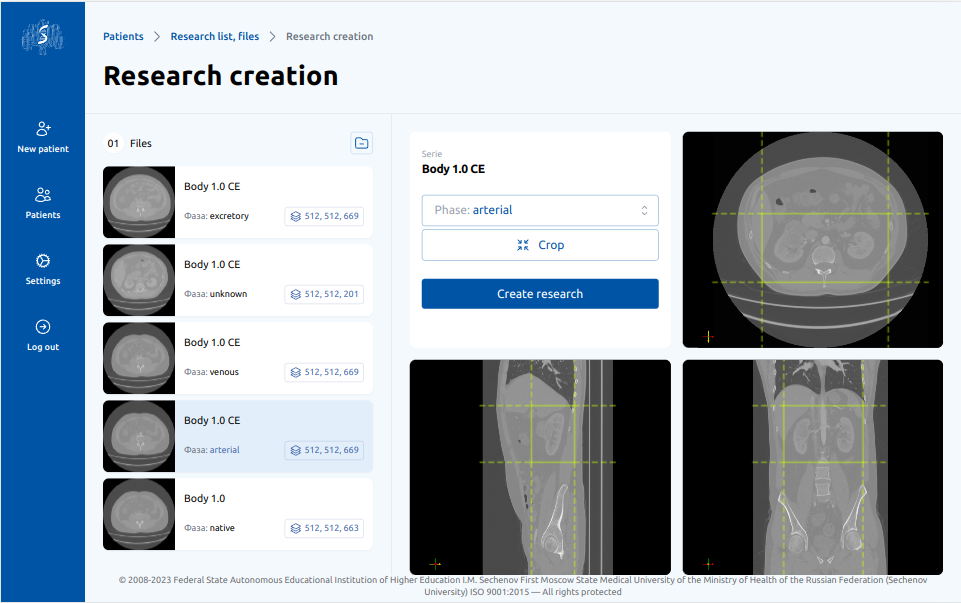

2

Выделение зоны интереса

Врач выбирает зону интереса для разметки